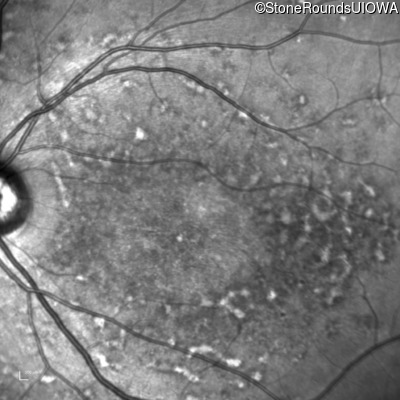

Blue Autofluorescence - Left - 20/150

Exemplar